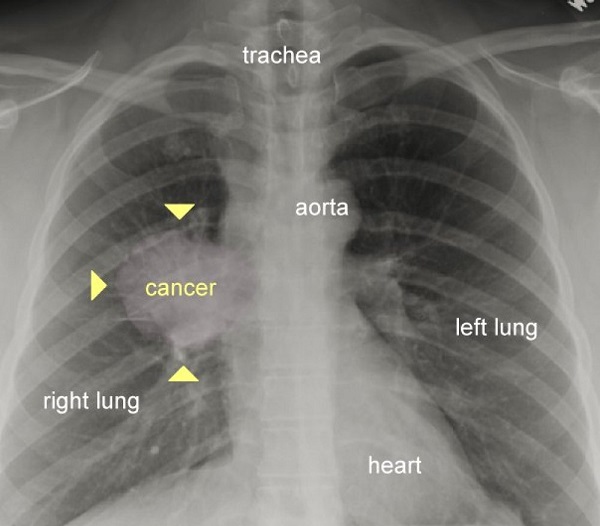

سرطان ریه

تاثیر سیگار کشیدن بر ریه‌ها به روایت تصویر

در این تصویر نقطه سرطانی در ریه به خوبی قابل مشاهده است. یک ریه سالم فاقد هر گونه تاری یا نقاط بزرگ است.